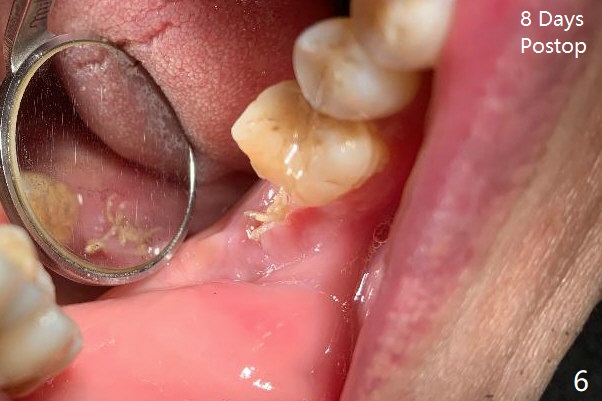

After removing the fractured apices of the tooth #31 (Fig.1,2), it is extremely difficult to start osteotomy with 7.3 mm stopper free hand. Since sticky bone (Fig.3,4) and PRF membrane are available, socket preservation is performed with bone condenser and PGA (Fig.5). If a surgical guide were fabricated, immediate implant would finish quicker. The socket opening is almost closed without pain or swelling 8 days postop (Fig.6). Clinically, the ridge is apparently wide with enough keratinized gingiva 4.5 months postop. The original ridge height seems to restore as the sticky bone undergoes condensation vertically (Fig.7, as compared to Fig.5). With bone graft, a 1.5 mm longer implant could be placed (Fig.8). The gingival pocket (Fig.9 white dashed line) seems to be an excellent cultivation bed for bone graft, although the latter also undergoes buccolingual shrinkage coronally (Fig.10).